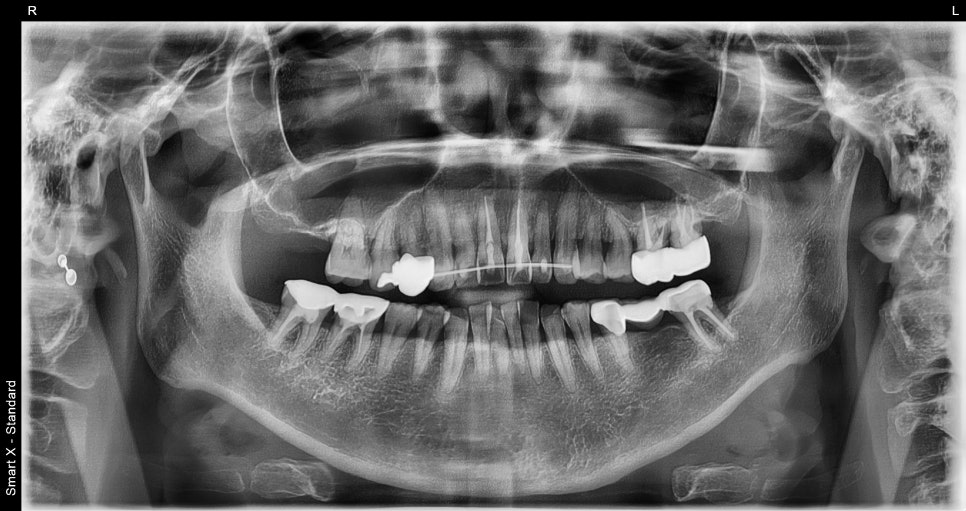

단순한 상처로 보였지만, CT 촬영 결과

앞니 주변 치조골 골절과 치아 변위가 확인되었습니다.

해당 환자분 또한

파노라마와 CT 진단에서

앞니 두 개 주변 치조골 골절과 치아 위치 변위가

명확히 확인되었습니다.

즉시 전문적인 고정이 필요한 상태였습니다.